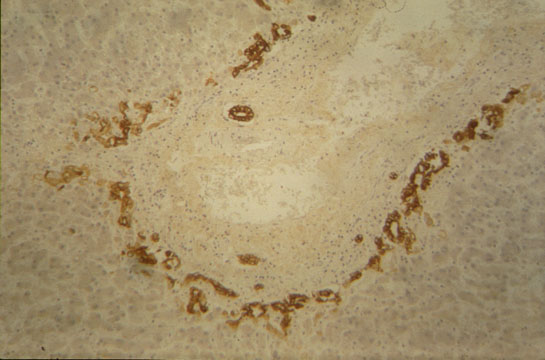

Fig 9 - BILE DUCTULES, CHOLANGIOLES, CANALS OF HERING

In the periportal region the biliary tree takes origin. The bile canaliculus lined by hepatocytes meets the ductule, first lined by hepatocytes and ductal epithelium, then lined only by ductal cells. They penetrate the portal space and connect with the interlobular bile duct. Bile ductules have a basal lamina. The ductal epithelium is cuboidal with light stained cytoplasm, dark nuclei and few cytoplasmic organelles.